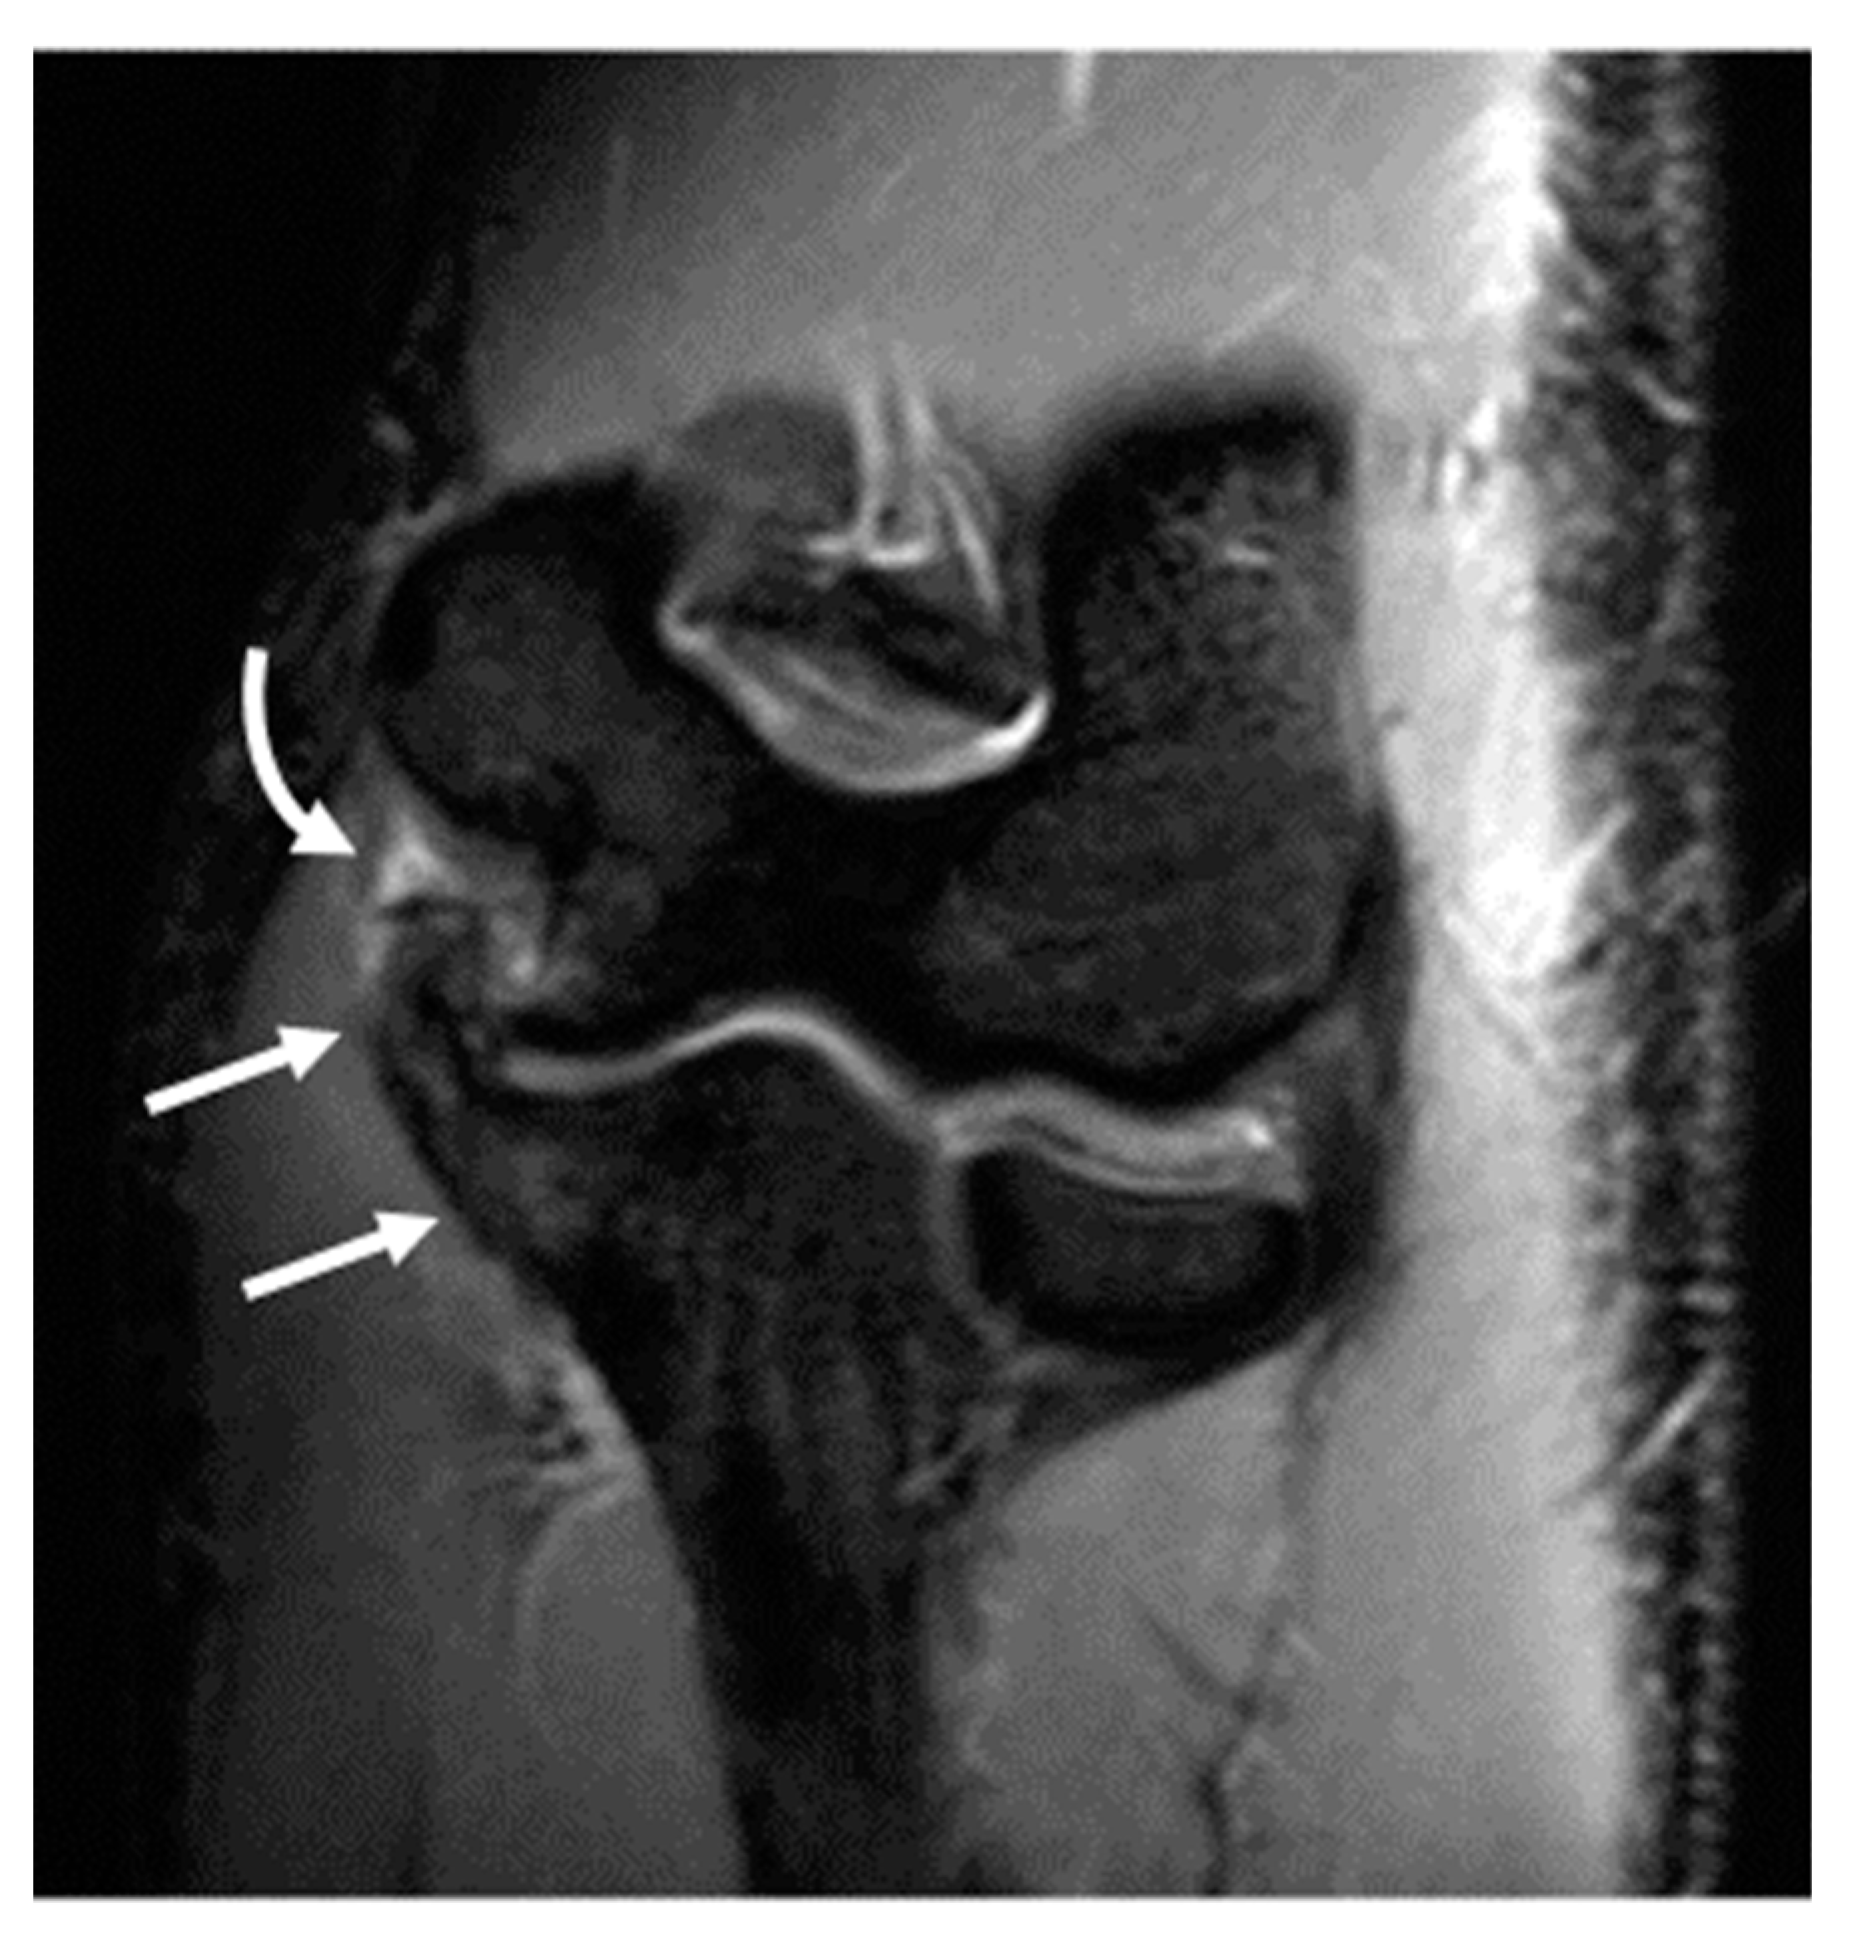

Figure 4.

A 16-year-old male right-hand-dominant baseball pitcher presenting with chronic right lateral elbow pain and acute medial pain after pitching. (A) AP radiograph demonstrating irregular lucency in the capitellum (arrow), compatible with osteochondritis dissecans (OCD), and a punctate joint body is seen in the radiocapitellar joint space (arrowhead). A small ulnar traction spur is visible along the sublime tubercle (curved arrow). (B) Coronal fat-saturated proton-density-weighted image demonstrates thickening and of the ulnar collateral ligament (curved arrow), with intrinsic high T2 signal and periligamentous edema, compatible with grade 2 injury. Of note, the lateral ulnar collateral ligament is intact and of normal morphology (arrowheads). (C) Sagittal fat-saturated T2 Cube image demonstrates an osteochondral lesion along the anterior capitellum with disruption of the articular cartilage and subchondral bone plate (arrow), and high T2 signal deep to the subchondral bone plate, indicating an unstable lesion.

Osseous abnormalities resulting from valgus extension overload were seen more frequently in younger athletes. Medial epicondylar apophysitis and acute apophyseal avulsion injuries from medial tension overload were only observed in athletes in subgroup 1 (Figure 3), although evidence of chronic avulsion injury was seen in the older age groups. Osseous findings from radiocapitellar overload were also seen most frequently in athletes in subgroup 1 (Figure 4), whereas posterior humeroulnar chondral injuries occurred with greatest frequency in subgroup 2.

Olecranon apophysitis was also only seen in athletes in subgroup 1 (Figure 5), with the exception of one athlete in subgroup 3 who had a chronic injury with associated nonunion of the olecranon apophysis, and olecranon stress reaction or fractures were observed with a higher frequency in subgroups 1 and 2 (12% and 24%, respectively), with a chronic injury seen in a single subject in subgroup 3. Other findings consistent with repetitive loading secondary to posteromedial shear and resultant degenerative changes in the posterior humeroulnar joint were observed with high frequency across all age groups, although this progressively increased with age. Specifically, humeroulnar osteophytes were observed in 62% of subjects in subgroup 1, 72% of subjects in subgroup 2, and 74% of subjects in subgroup 3 (Figure 6). This is in contrast to controls, where only 17% of subjects demonstrated posterior humeroulnar osteophytes.